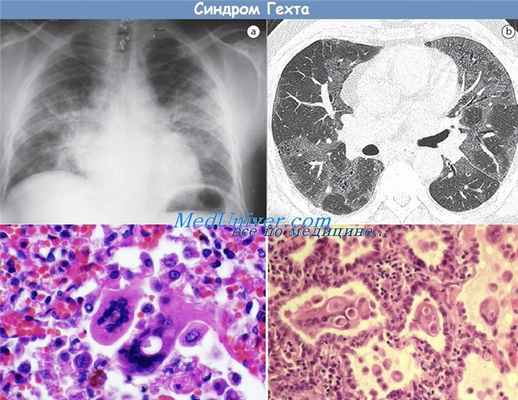

Тяжелая гигантоклеточная пневмония, вызванная вирусом кори, была описана у детей, ранее иммунизированных инактивированным вирусом кори и в дальнейшем имевших контакт с естественной инфекцией [Fulginiti et al., 1967].. У этих больных очень высокий титр ингибиции гемагглютинации, и авторы предположили, что такая избыточная реакция, возможно, представляет собой реакцию Артюса с образованием иммунных комплексов в легких у лиц с гипериммунной реакцией.